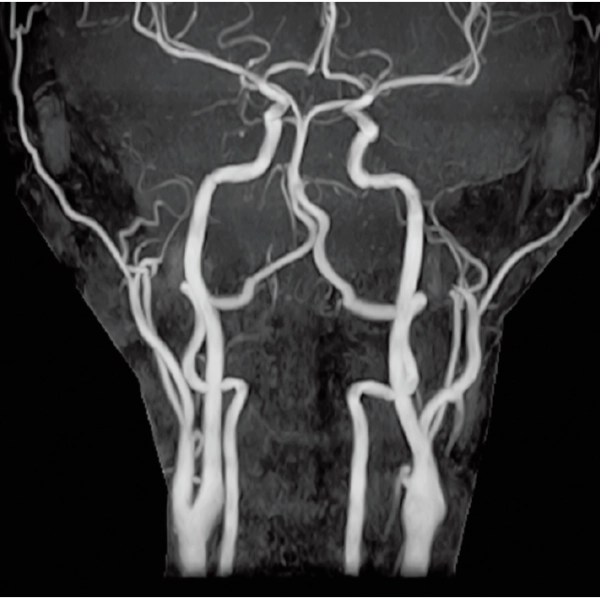

3DTOF MRA (MIP), 1:26

3DTOF MRA RADAR (MIP)

3D MRCPA (MIP)